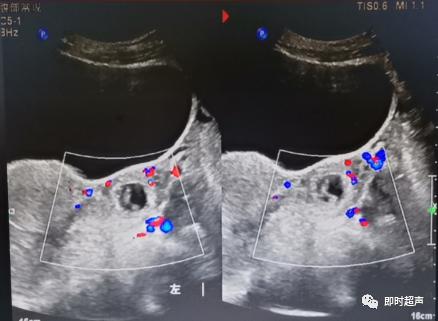

超声下腹腔大量液性暗区,扫查发现左侧附件区一孕囊样回声,其内可见似胚芽组织,CDFI:未见明显血流信号,考虑:1.左侧附件区异位妊娠2.盆腔大量液性暗区,性质待定。建议HCG检查。

血压120/80mmHg,插导尿管,查尿HCG(+),确定怀孕。随后完善各项检查,行急诊开腹手术,发现左侧输卵管壶腹部一大小约29×35mm包块,与B超数据相吻合。确定盆腔积液为大量血液,量约1800ml。患者各项生命体征平稳,转危为安。